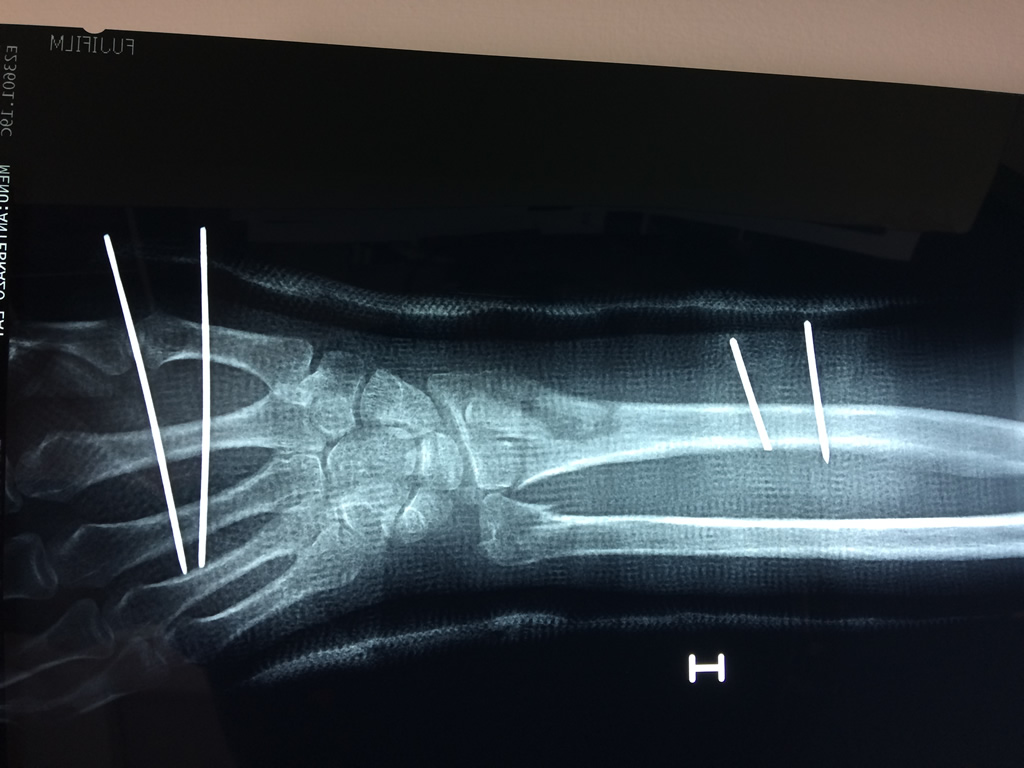

Cirugías de Muñecas

Los procedimientos más comunes en cirugía de la mano son aquellos destinados a reparar traumatismos, incluyendo lesiones de tendones, nervios, vasos sanguíneos, y articulaciones; huesos fracturados; y quemaduras, cortes, y otros daños de la piel.